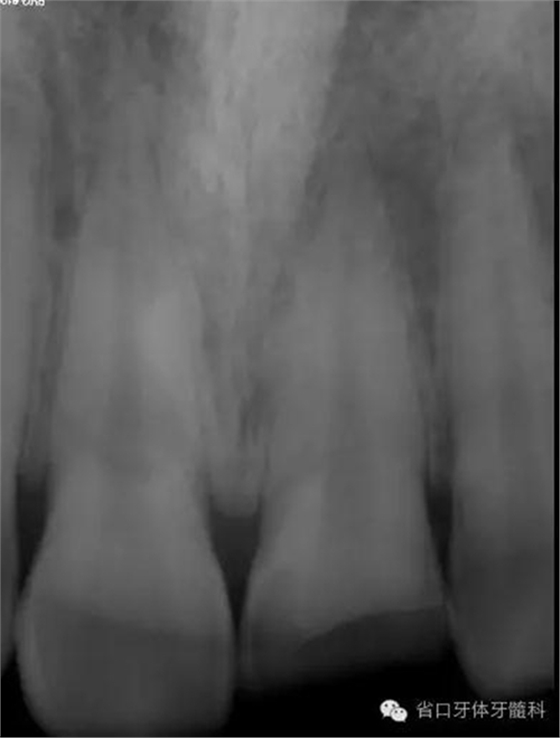

術前X線片

X線片示21冠折,根段未見明顯牙折影像。